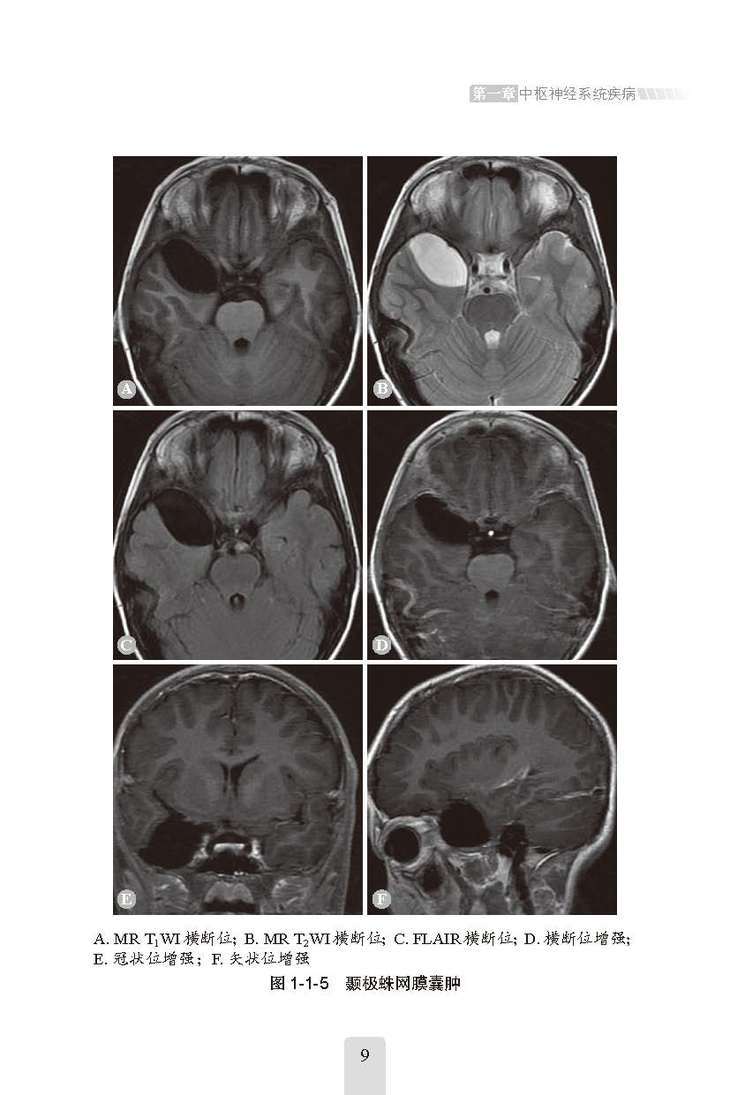

全书共9章、52节,主要讲述了中枢神经系统疾病、头颈五官系统疾病、呼吸系统疾病、循环系统常见疾病、消化系统常见疾病、泌尿系统与肾上腺疾病、腹膜后间隙及腹腔内病变、生殖系统与乳腺常见疾病、骨关节系统疾病,从每种疾病的“影像学检查方法选择”“临床概述”“影像学特点”和“鉴别诊断”等方面进行论述,详细讲解了每种疾病的各个影像学特点,并对易混淆疾病做了全面的鉴别诊断分析,避免了漏诊、误诊的可能。